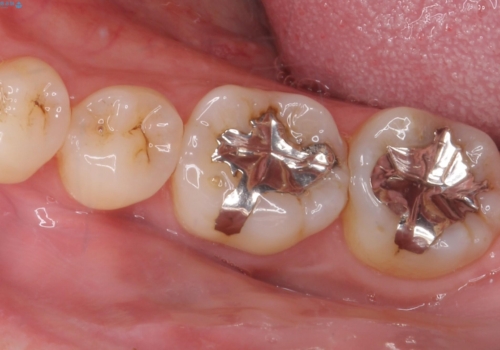

- 治療計画

- 前歯が大きいのを揃えたいとのことでした。

少し削って長さを短くして様子を見ましたが、どうしても気になるとのことでした。

隣の前歯が小さいため、4本被せてバランスをとりました。

4本セラミックにすると大きさだけでなく、色も揃えられるのでおすすめです。